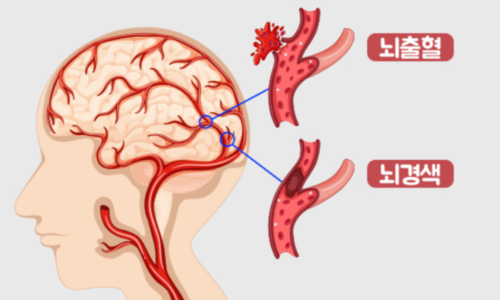

뇌혈관이 막히거나 터지는 질환을 통칭하는 것이 뇌졸중이고 그 중 뇌혈관이 막히는 것이 뇌경색 그리고 뇌혈관이 터지는것을 뇌출혈이라고 합니다. 뇌졸중은 영구적인 손상이 많고 증상에 따라 전신이나 신체 일부 기능이 마비되는 등의 심각한 후유증이 남는 무서운 질병인데요 오늘은 뇌경색 초기증상 및 뇌경색 치료방법에 대해 알려드리겠습니다.

뇌경색 원인은 동맥경화증으로 시작합니다. 병이 든 혈관 어떤 곳에든 핏덩어리가 생겨나면 심장에서 뇌로 흐르는 혈액의 흐름을 방해하게 됩니다. 만약 핏덩어리가 내경동맥이나 뇌혈관을 막게 되면 치명적인 뇌 손상을 입을 수 있습니다. 이렇듯 갑자기 혈관을 막는 경우도 있으나, 혈전에 의하여 점차 혈관 너비가 좁아지면서 허혈성 뇌졸중이 유발되는 경우도 있습니다.